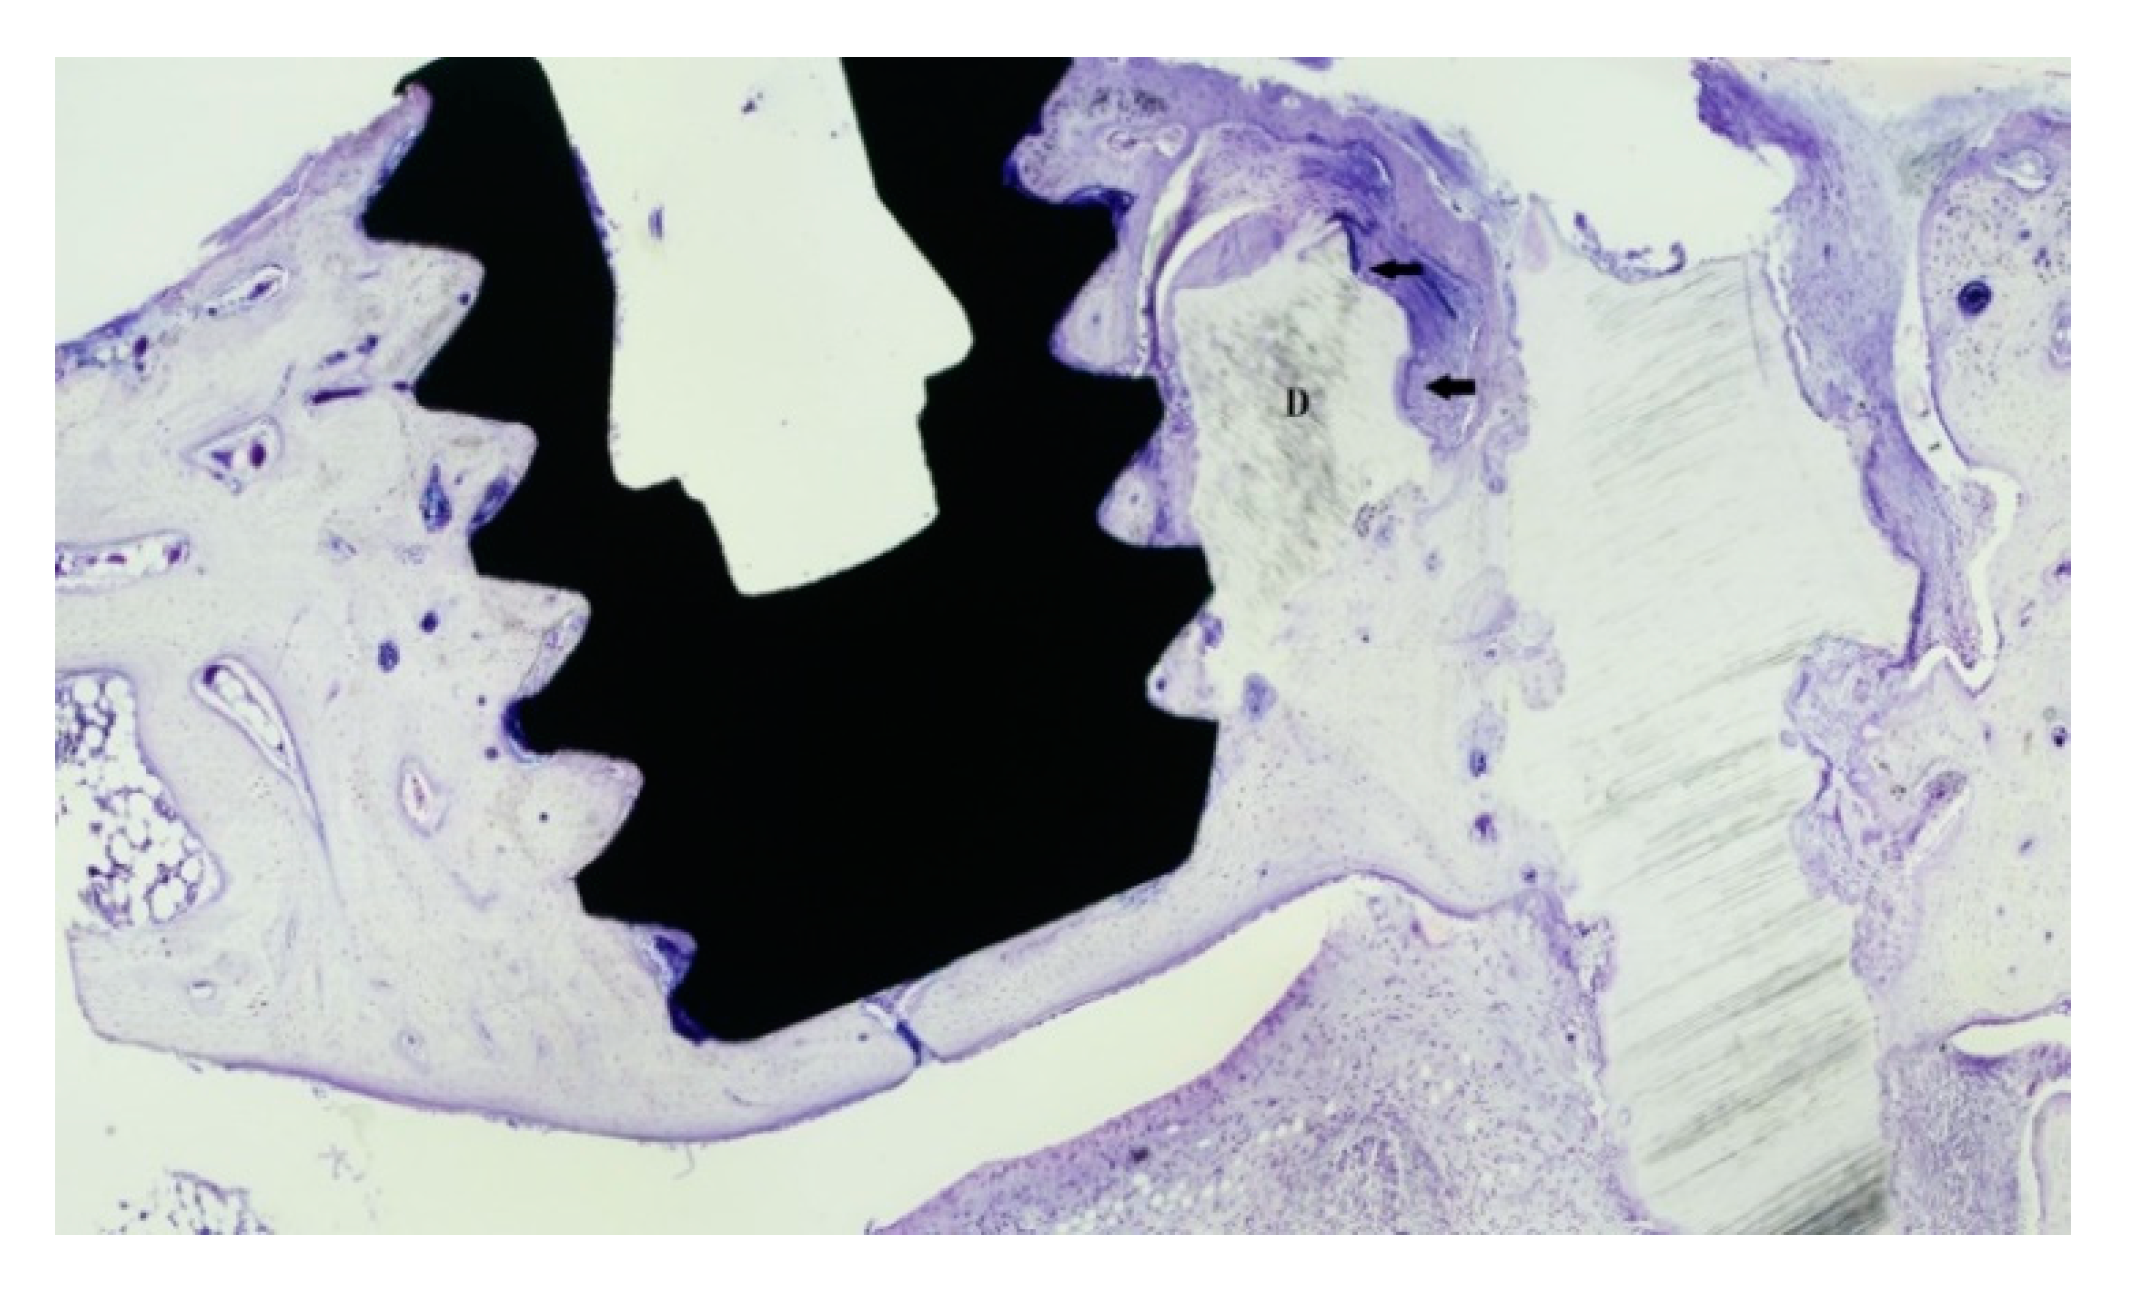

3.1. Descriptive Characterization of Dentin Block

3.2. Bone Healing